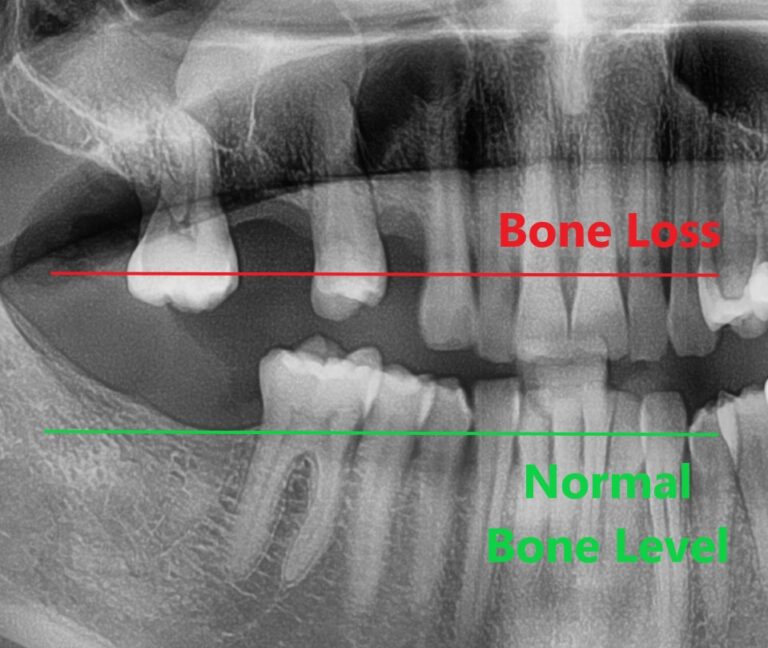

Bone loss in the jawbone is one significant problem that naturally occurs once a tooth is lost. This can compromise the integrity of neighboring tooth roots and tooth stability, and it is also a large part of what causes the “sunken” look that is seen in people who have lost several or all of their teeth.

Dental implant placement can help generate bone growth in the area around the implant, which not only strengthens the bone and builds support, but can also alleviate the sunken look that can occur with bone loss in the jaw. This process is known as osseointegration and is a significant benefit of implant placement because it can also help prevent future bone loss.